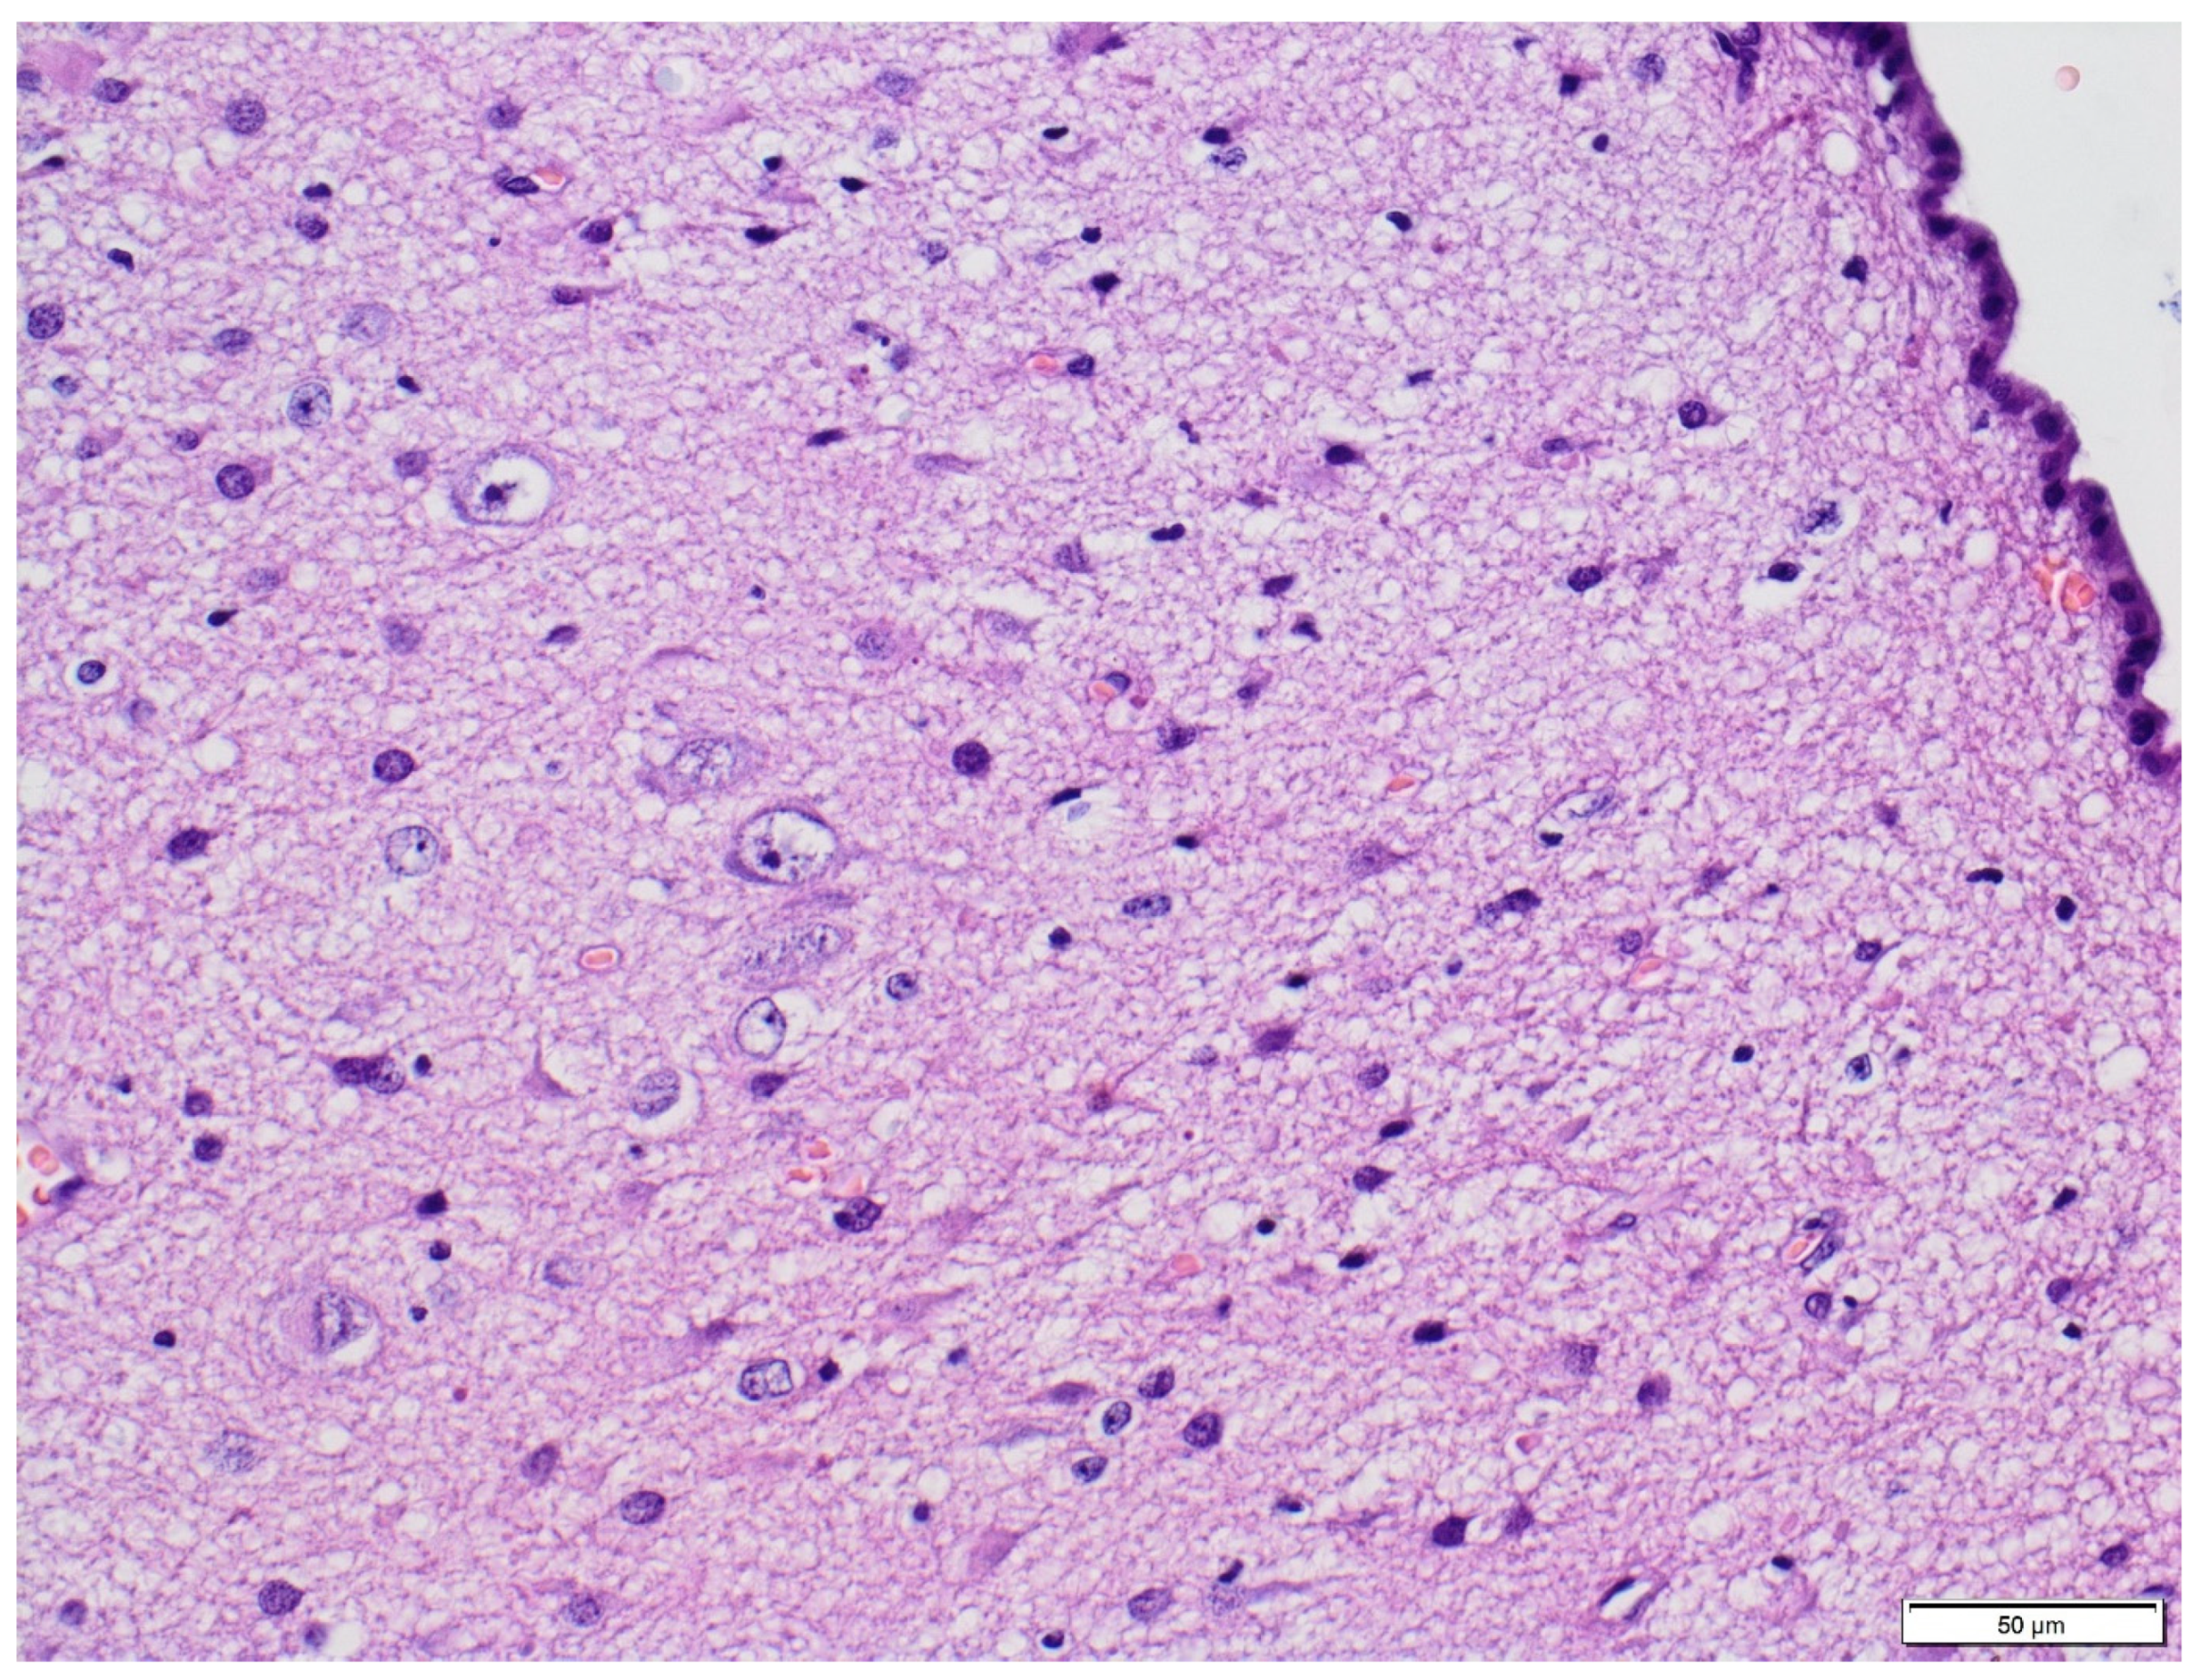

3.1. Clinical and Pathology Report